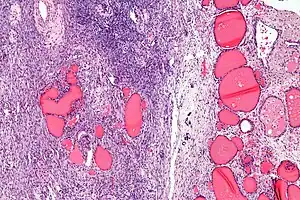

Low magnification Struma ovarii -